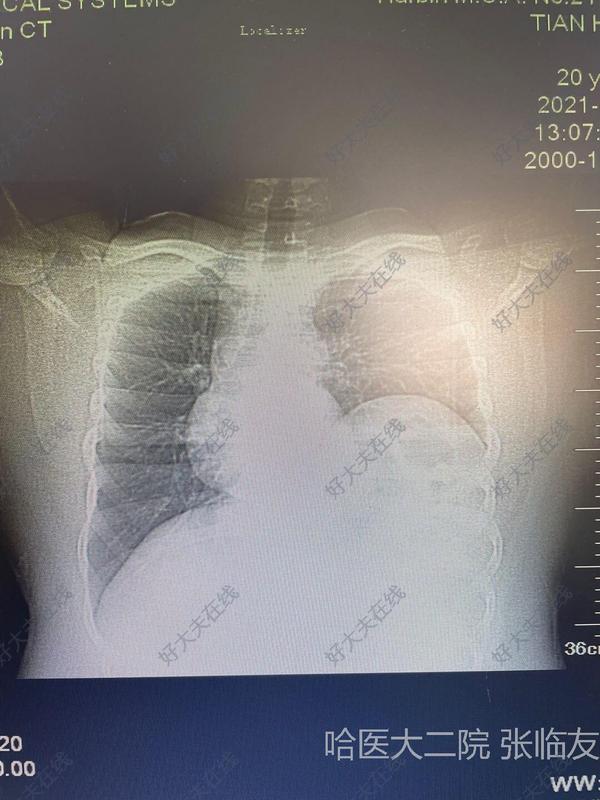

膈肌腫瘤屬于少見(jiàn)疾病,包括良性腫瘤和惡性腫瘤。良、惡性膈肌腫瘤發(fā)病率大致相等,膈肌良性腫瘤包括囊腫、纖維瘤、脂肪瘤,其中以脂肪瘤最常見(jiàn)。膈肌最常見(jiàn)的惡性腫瘤為肉瘤。除原發(fā)腫瘤外,繼發(fā)性膈肌腫瘤并不少見(jiàn)。來(lái)自胸內(nèi)和腹內(nèi)惡性病變均可直接侵及膈肌,任何侵犯或轉(zhuǎn)移到胸膜、腹膜的病變也可累及膈肌。主要惡性腫瘤包括間皮瘤、肺癌、侵襲性胸腺瘤、肝癌、食管癌和卵巢癌。良性病變?nèi)缱訉m內(nèi)膜異位癥偶也可累及膈肌。 據(jù)統(tǒng)計(jì),膈肌腫瘤發(fā)病男女比例為1.1:1。良、惡性腫瘤比例為3:2。良性腫瘤依次是囊腫(支氣管來(lái)源、間質(zhì)來(lái)源占17.7%)、脂肪瘤(11.2%)、神經(jīng)鞘瘤(5.6%)。惡性腫瘤依次為纖維肉瘤(9.3%)、平滑肌肉瘤和其他肉瘤(各4.7%)。左、右側(cè)膈肌腫瘤發(fā)生率大致相等。 良性腫瘤多無(wú)癥狀,在查體X線檢查時(shí)偶然發(fā)現(xiàn)。惡性腫瘤常有胸痛,腫瘤較大擠壓肺臟可引起呼吸困難,侵犯膈神經(jīng)時(shí)疼痛可放射至肩部和上腹部,腫瘤侵犯肺組織可有咳嗽、咯血或氣短。腫瘤向腹腔生長(zhǎng)可產(chǎn)生胃腸道癥狀和肝區(qū)疼痛。也有近1/3患者無(wú)癥狀。 由于橫膈區(qū)解剖較為復(fù)雜,膈肌病變術(shù)前往往診斷不清。它容易與肺、縱隔特別是肝臟病變相混淆。膈肌腫瘤常以發(fā)生點(diǎn)為中心,向各個(gè)方向發(fā)展,累及周圍的組織、器官,有時(shí)很難與膈上、膈下、肺臟基底段、心臟、縱隔等處的腫瘤鑒別開(kāi)來(lái)。 X線檢查發(fā)現(xiàn)膈肌上有邊緣光滑的球形或塊狀陰影,惡性者呈分葉狀,隨膈肌上下活動(dòng),肺、肝或脾受腫瘤擠壓而移位。惡性腫瘤侵犯膈神經(jīng),引起膈麻痹,橫膈升高且無(wú)運(yùn)動(dòng),常伴有胸腔積液或腹水。CT是目前診斷膈肌腫瘤的主要方法,大部分病例經(jīng)CT檢查可以確診,但是當(dāng)腫瘤巨大致周圍結(jié)構(gòu)不清,CT亦難以確切診斷。 (女性患者,33歲,自感左季肋部不適2年,發(fā)現(xiàn)左前胸壁腫物1個(gè)月入院,圖一CT顯示左前下胸腔內(nèi)腫物,大小18cm×15cm×12cm,橢圓形,與肌和前胸壁分界不清,行左后側(cè)切口開(kāi)胸,手術(shù)發(fā)現(xiàn)腫瘤來(lái)源于膈肌胸骨部和肋部,侵及膈肌、心包和部分肋骨。完整切除腫瘤、部分心包和肋骨,滌綸片修補(bǔ)膈肌、心包和胸壁缺損。術(shù)后病理診斷“膈肌纖維瘤”) (圖二為矢狀位CT像顯示左膈肌腫瘤) 一旦明確膈肌腫瘤,均應(yīng)采取手術(shù)治療。一般說(shuō)來(lái),大多數(shù)腫瘤較小,切除和重建膈肌并不困難。偶爾在擴(kuò)大切除或縫合有張力時(shí),需要補(bǔ)片替代膈肌缺損。切除后重建一般用不可吸收材料修補(bǔ)。修補(bǔ)左側(cè)膈肌缺損時(shí)應(yīng)避免腹腔臟器疝入胸腔,右側(cè)由于肝臟保護(hù),疝入的機(jī)會(huì)較少。良性腫瘤和囊腫切除后,效果良好,隨診多年無(wú)復(fù)發(fā)。膈肌惡性腫瘤切除后常常需要進(jìn)行放療或化療,以預(yù)防腫瘤復(fù)發(fā)或轉(zhuǎn)移。

張臨友醫(yī)生的科普號(hào)2020年07月21日9382